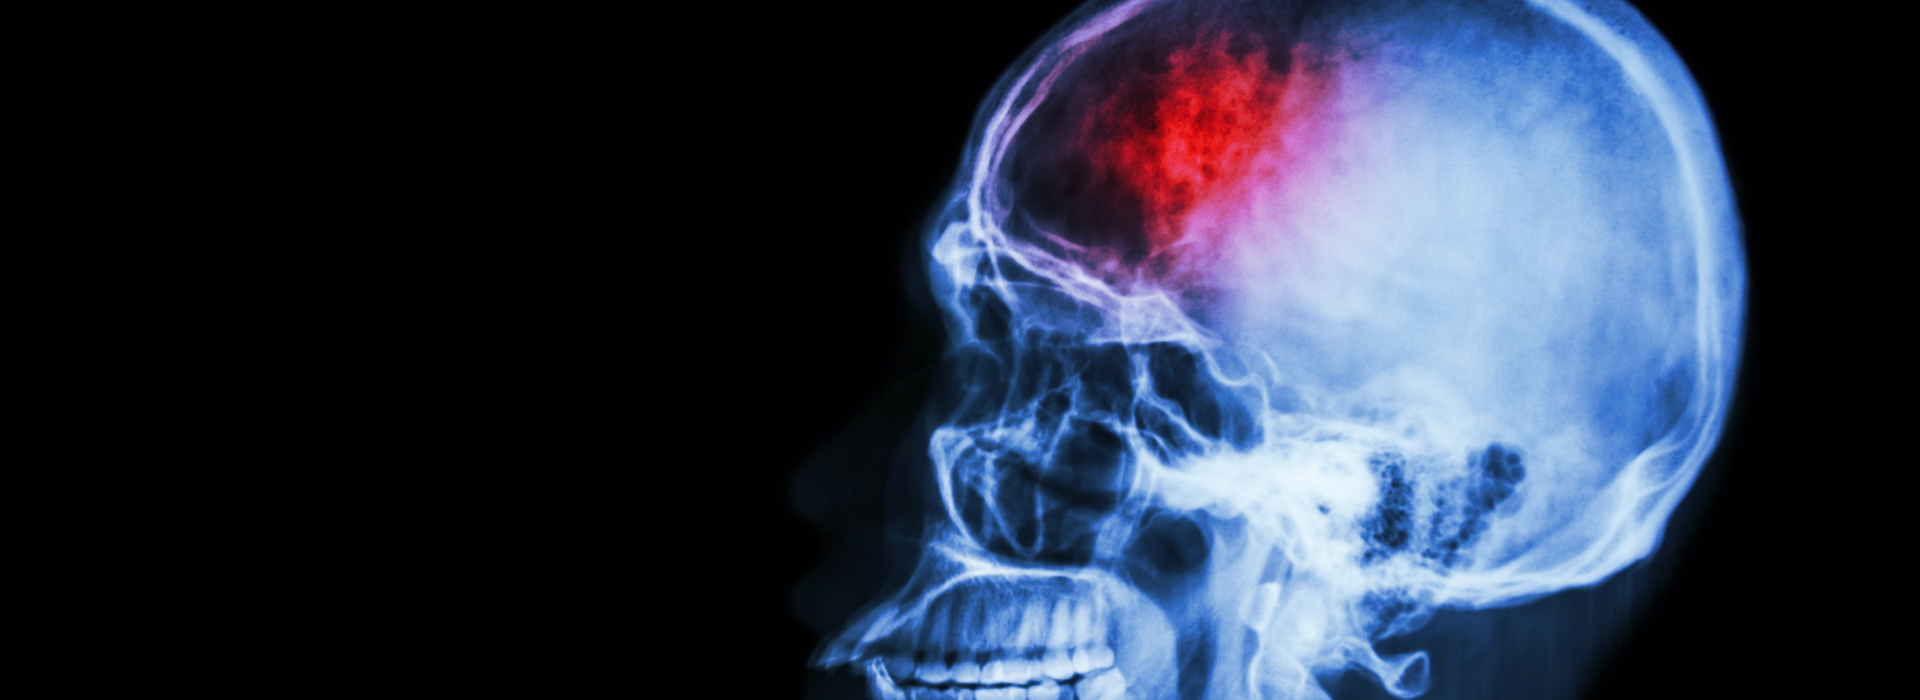

El ACV comprende un grupo de síntomas y signos secundarios a una lesión del cerebro (generalmente focal, transitoria o permanente), originado por la alteración del flujo sanguíneo cerebral el cual debe ser confirmado por imagen cerebral ya sea por TAC (tomografía axial computarizada) o resonancia cerebral; se divide en isquémica y hemorrágica. El ACV isquémico incluye el infarto cerebral y la isquemia cerebral transitoria (AIT). En el ACV hemorrágico están incluidas la hemorragia intraparenquimatosa, hemorragia subaranoidea espontánea, hematoma dural y epidural. Otra entidad que hace parte del ACV es la trombosis de senos venosos y venas cerebrales.

En el ACV isquémico, existe oclusión de un vaso cerebral con la consecuente obstrucción del flujo sanguíneo cerebral (FSC); se desencadena una cascada de eventos bioquímicos que inicia con la pérdida de energía y que termina en muerte neuronal. Después de la oclusión, el núcleo central o core se rodea por un área de disfunción causada por alteraciones metabólicas e iónicas, con integridad estructural conservada, a lo que se denomina “penumbra isquémica”, la cual podemos aún rescatar si actuamos a tiempo. La isquemia cerebral es un fenómeno dinámico y complejo, que se produce de manera abrupta, sin embargo, las alteraciones moleculares que se producen en las células ocurren de manera secuencial a lo largo de un tiempo que depende de la gravedad de la isquemia, de que ésta sea permanente o transitoria y de que se apliquen medidas terapéuticas dirigidas a proteger el tejido afectado.